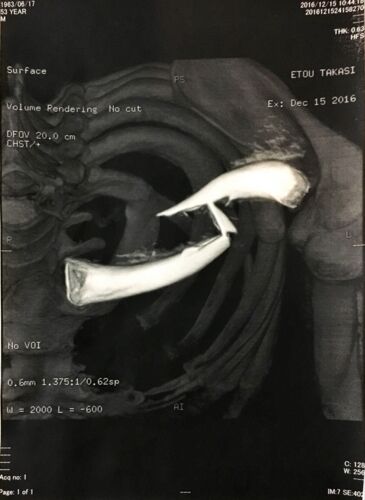

12月15日 救急車で病院に運ばれる頃には自分でも骨折してしまったなという実感が出てきた。肩をだらんと下げたまま動かせない。とにかく痛い。レントゲンやらの検査を行ってから正式に医師から「左鎖骨骨折、肋骨骨折、肺の損傷」を伝えられました。骨折だけ…

大腿骨頸部骨折について

入院3日目、手術は無事成功

手術に備えて昨日髭を剃りました。そう言えば前回手術したときも剃った気がする。顔色の変化がわかりやすいためです。 寝たきりなのでトイレにも行けない。ということで手術に備えて浣腸。(T_T) 26日の午後12:10、手術が行われました。全身麻酔だったので、…